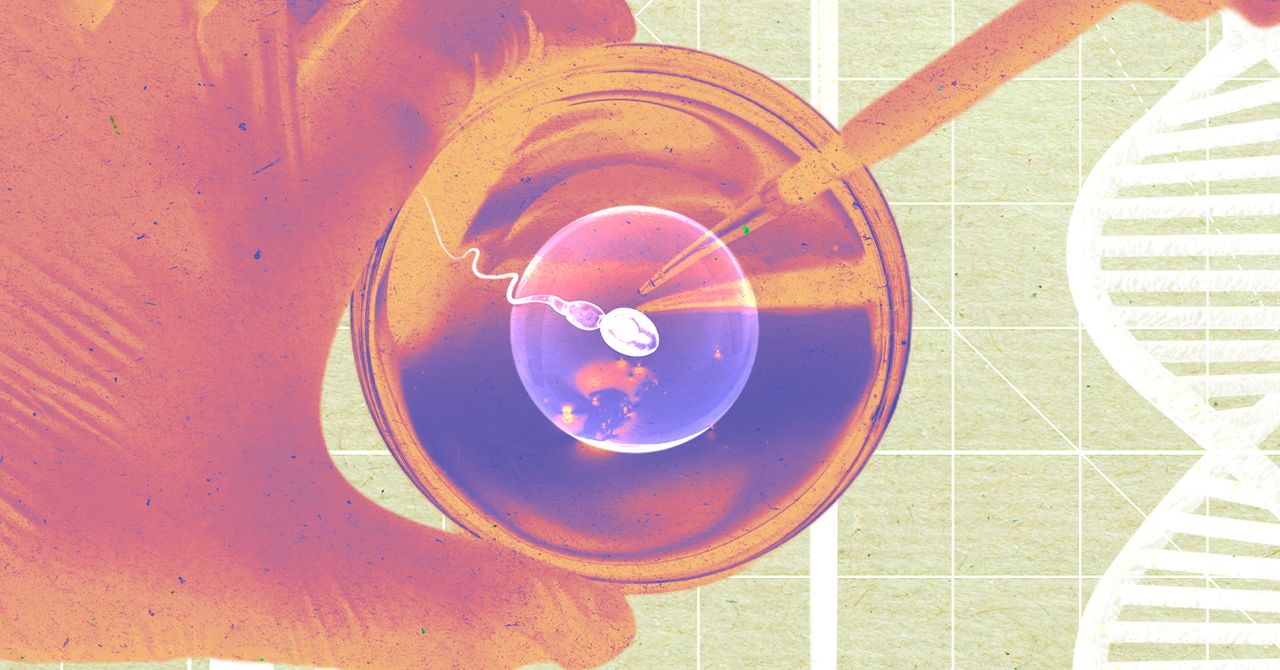

Early tests have shown that lab-made sperm appear “effectively identical” to naturally made sperm, Pastusak says. However, the procedure is not yet ready to be used to initiate pregnancy. Paterna created the embryos as an early test to verify that the sperm made in the laboratory were indeed viable. The company plans to conduct a larger, more comprehensive study including infertile men. Paterna will extract sperm from ejaculate or testicular tissue and use his method to generate sperm for men. From there, the company will use both extracted sperm and laboratory-grown sperm to fertilize eggs in the laboratory, compare fertilization rates between the two groups, and analyze the resulting embryos for physical and genetic abnormalities.

The Paterna technique is designed to replace this procedure, instead a small biopsy of testicular tissue is taken in a doctor’s office. This tissue will be sent to Paterna, who will create sperm in the laboratory. The company plans to charge between $5,000 and $12,000 for the procedure.